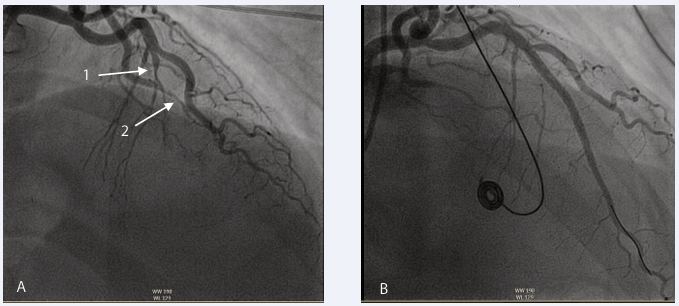

She was urgently returned to the catheter lab, where the right radial artery was accessed using a 6 French sheath and VL 3.5 guide was taken. Coronary angiography showed proximal LAD occlusion with contrast “hang-up,” indicating haematoma, and progression of the SCAD, requiring further treatment.

A run-through wire was advanced into the LAD without complications, and a 4.0 x 12 mm Wolverine Cutting balloon was used to release the hematoma and restore TIMI 3 flow.

A 3.5 x 36 mm Biomatrix stent was deployed to cover the proximal LAD, overlapping with the previous mid-LAD stent. IVUS confirmed LAD diameter at 4.5 mm and a 4.75 mm diameter at the left main stem. (Distally with previous LAD stent and proximally to cover whole LMS.) (IVUS measurement). A 3.5 x 29 mm Biomatrix stent was deployed to overlap with the ostium of the left main stem. A 4.5 mm NC balloon was used at high pressure from just distal to the diagonal to the LAD ostium (Figure 4 and Figure 5).

Figure 4: Return to cath lab. (A) Anterio posterior caudal view showed SCAD in LAD back to LMS with no flow in distal LAD. (B) Anterio posterior Cranial showed no flow in LAD (Dye hang up). (C) Wolverine cutting balloon 4.0x12 at 6 atm pressure was used to release the hematoma in LMS and Proximal LAD. (D) The result after PCI with 2 Drug eluting stents from LMS down to mid LAD.